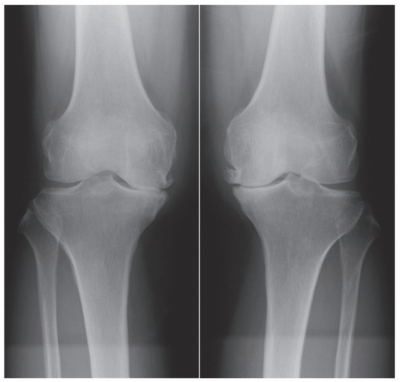

身長152cm、体重70kg。BMI 30.3。体温36.4℃。脈拍84/分、整。血圧126/68mmHg。呼吸数14/分。神経診察で異常を認めない。両膝関節腫脹を認めない。両膝の内側関節裂隙に圧痛を認める。右膝関節の可動域は、屈曲120度、伸展−10度である。左膝関節の可動域は、屈曲130度、伸展−5度である。両膝関節立位正面エックス線写真を別に示す。

治療法として適切なのはどれか。3つ選べ。

a. 体重の減量

b. 下肢筋力訓練